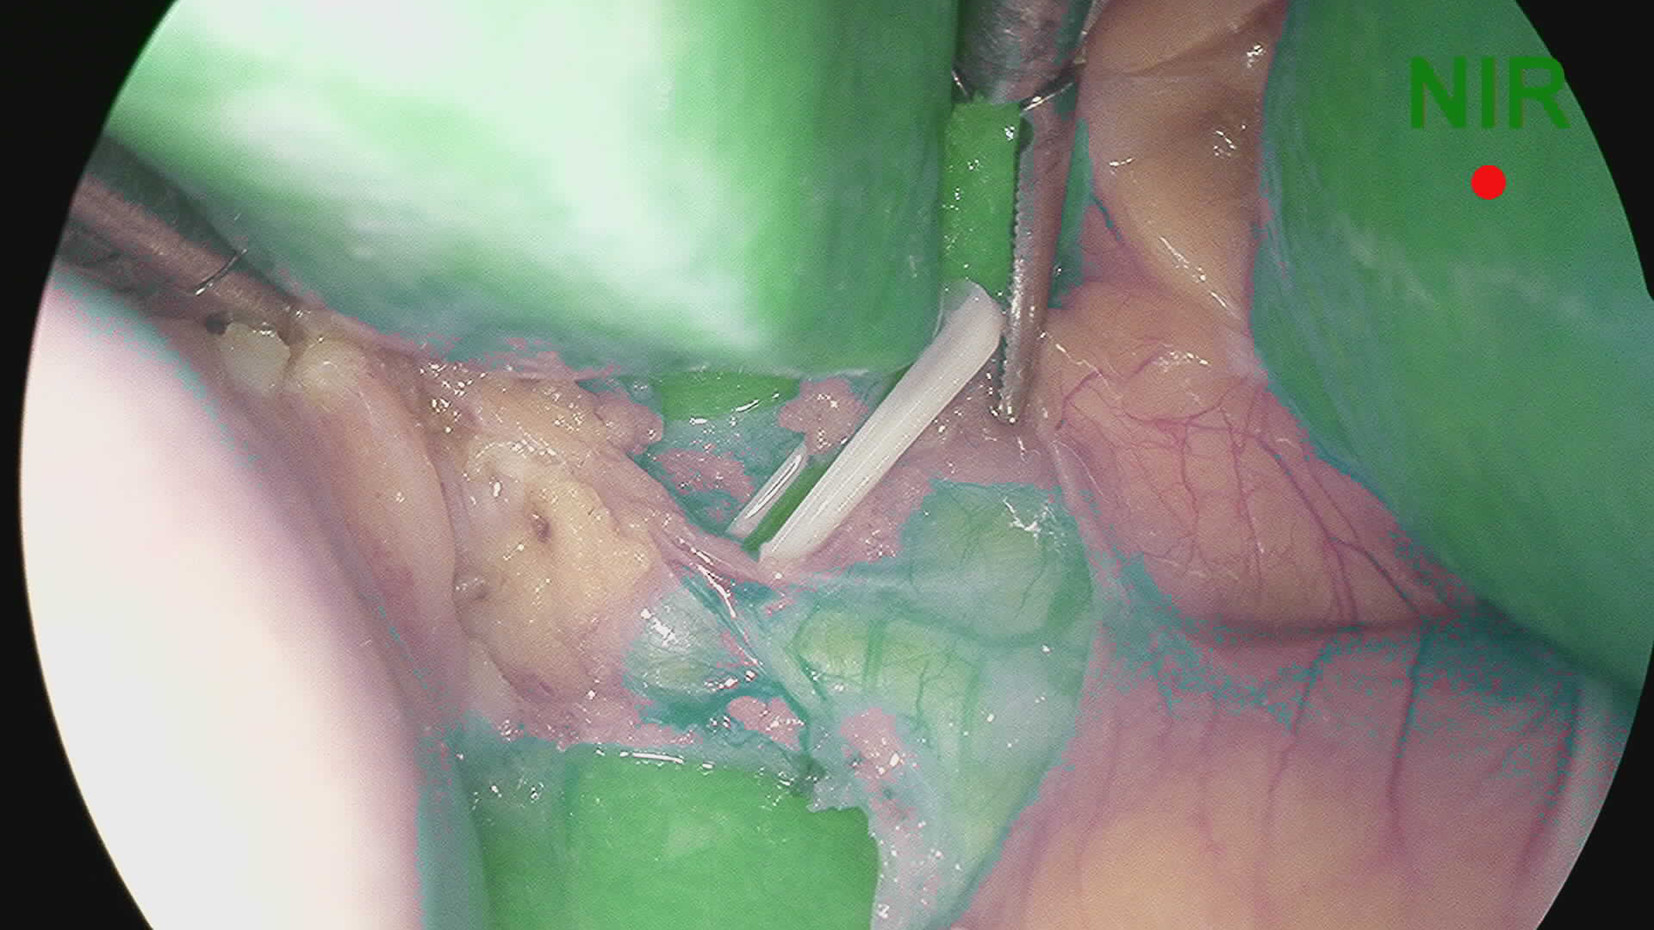

Application value of indocyanine green fluorescence imaging in laparoscopic cholecystectomy of difficult gallbladder

Qizhu FENG, Siyu WANG, Chao ZHANG

2022, 38(11): 2537-2541. DOI: 10.3969/j.issn.1001-5256.2022.11.019

Abstract(1354) HTML (240) PDF (2744KB)(76)

Abstract:

Objective  To investigate the clinical utility of indocyanine green (ICG) fluorescence imaging in difficult laparoscopic cholecystectomy (LC).  Methods  The clinical data of LC patients from October 2021 to December 2021 in the First Affiliated Hospital of Anhui Medical University were retrospectively analyzed. Based on whether ICG fluorescence imaging was used and whether gallbladder difficulties were detected, the patients were divided into four groups: ICG common gallbladder (Group A), ICG difficult gallbladder (Group B), common gallbladder (Group C), and difficult gallbladder (Group D). The operative time, intraoperative bleeding, length of hospital stay, hospitalization cost and postoperative complications were compared. Comparison of normally distributed continuous data between groups was performed by t test. Comparison of categorical data between groups was performed using the chi-square test or Fisher's exact probability method.  Results  The operative time, intraoperative bleeding, length of hospital stay, hospitalization cost and intraoperative complications in group A were comparable to those in Group C (all P > 0.05). The operative time and intraoperative bleeding were (75.41±12.96) min and (18.27±6.97) mL in group B, vs (106.78±19.21) min and (23.99±8.43) mL in group D, respectively, and the differences were statistically significant (all P < 0.05), while the length of hospitalization, hospitalization cost and postoperative complications in group B were comparable to those in group D (all P > 0.05).  Conclusion  The benefits of ICG fluorescence imaging during LC in patients with the common gallbladder are not obvious. However, in difficult gallbladder cases, ICG fluorescence imaging can improve biliary tract exposure and reduce operation time and intraoperative bleeding.